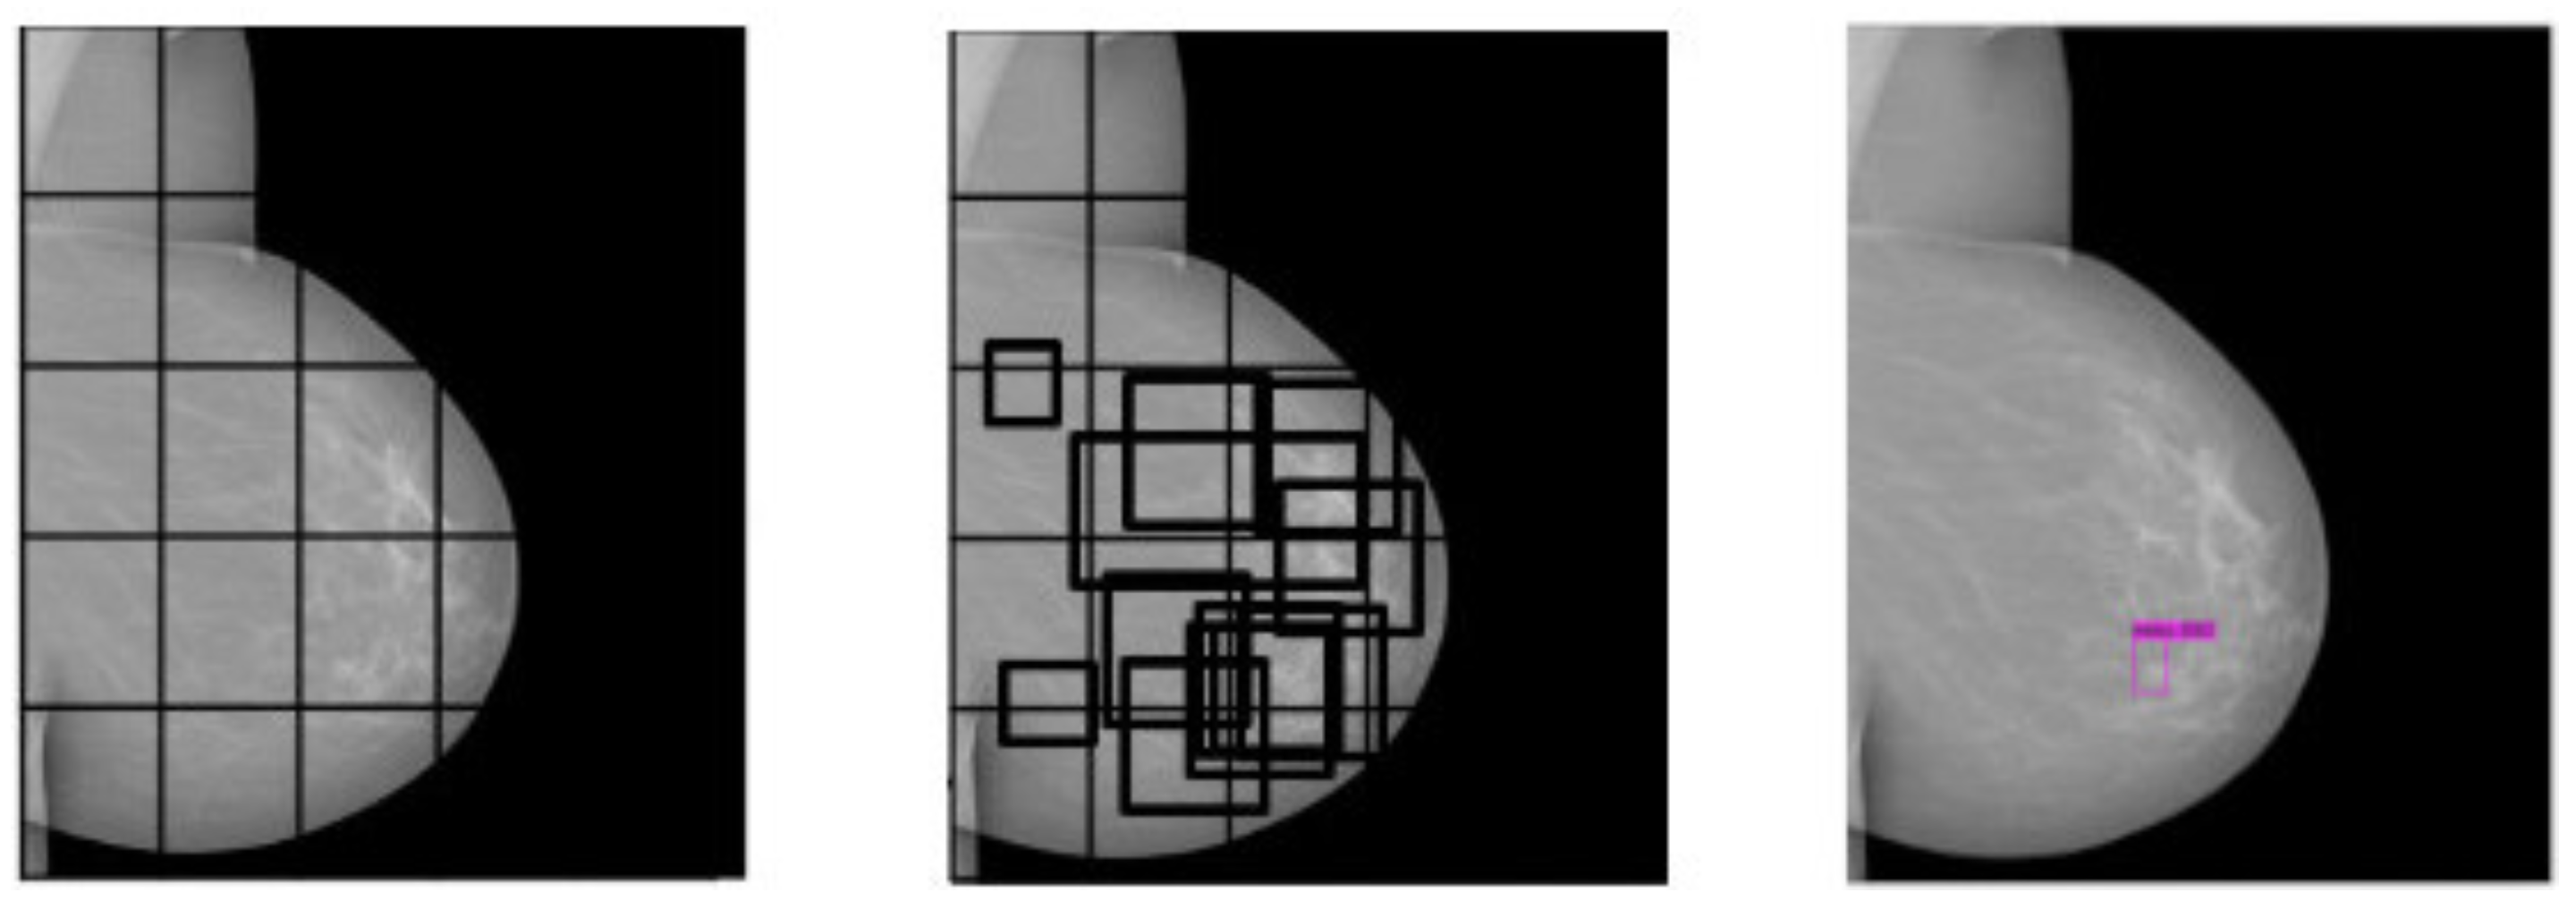

2.4. Mass Location and Segmentation

Since the ROI is focused on the mass, this must be separated from the rest of the breast area. For this task, a pretrained convolutional neural network (CNN) model YoloV4 (You Only Look Once V4) was used for locating the mass area [24], using the configuration parameters of Table 1. In its working process, YoloV4 divides the image into quadrants to identify the ROI, marking regions where a significant similarity is found according to its probability value. Images were resized to 416 × 416 to improve the online training of the model [25]. As an output, YoloV4 returns the region most likely to contain the object of interest (mass). Figure 3 depicts an example of the general ROI detection process, where the bounding box in magenta indicates the most likely region containing a mass with its respective probability value.

Figure 3. From quadrant analysis (left) to similarity estimation among regions (center) and the selection of the region with the most significant probability represented in the magenta bounding box (right) with YOLOV4.